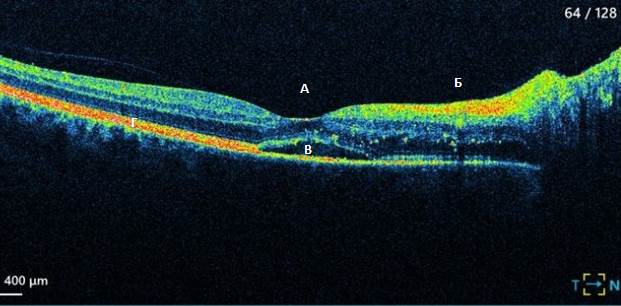

Диагностика зрения: Когерентная томография сетчатки